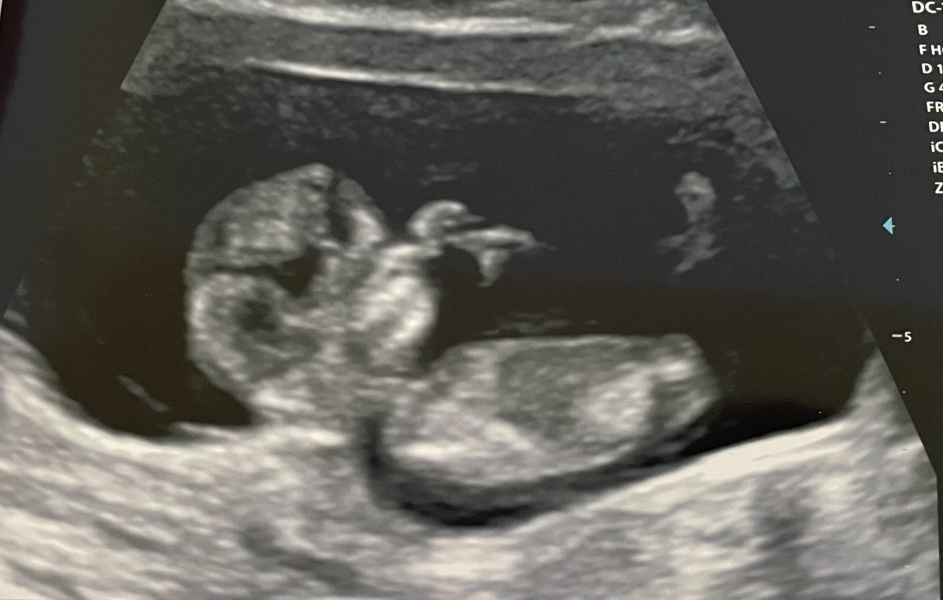

KittyFantastica · 04/08/2024 12:29

Just going to leave this here as a little positive update. I'm still mostly keeping my head low and my heart hopeful.

We're 11 weeks today and we are measuring 11+4. Baby was moving around, stretching and sucking their thumb. It's the furthest we've ever got, and we were in floods of tears.

Keeping you all in my heart ❤️